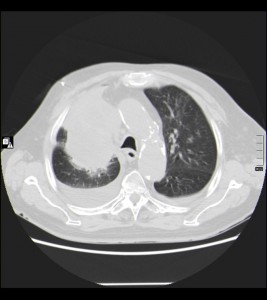

* Encontramos una masa pulmonar parahiliar superior derecha de unos 10 x 6 cms, que contacta con mediastino al que infiltra;también vemos nódulos pulmonares bilaterales compatibles con metástasis de la masa parahiliar derecha.

* Derrame pleural bilateral algo mayor derecho, con diámetro máximo de 2 cms.

* No derrame pericárdico.

* Se observan varias adenopatías mediastínicas que oscilan entre 6 mm y 15 mm en su eje corto; Las estructuras vasculares mediastínicas presentan un calibre normal.